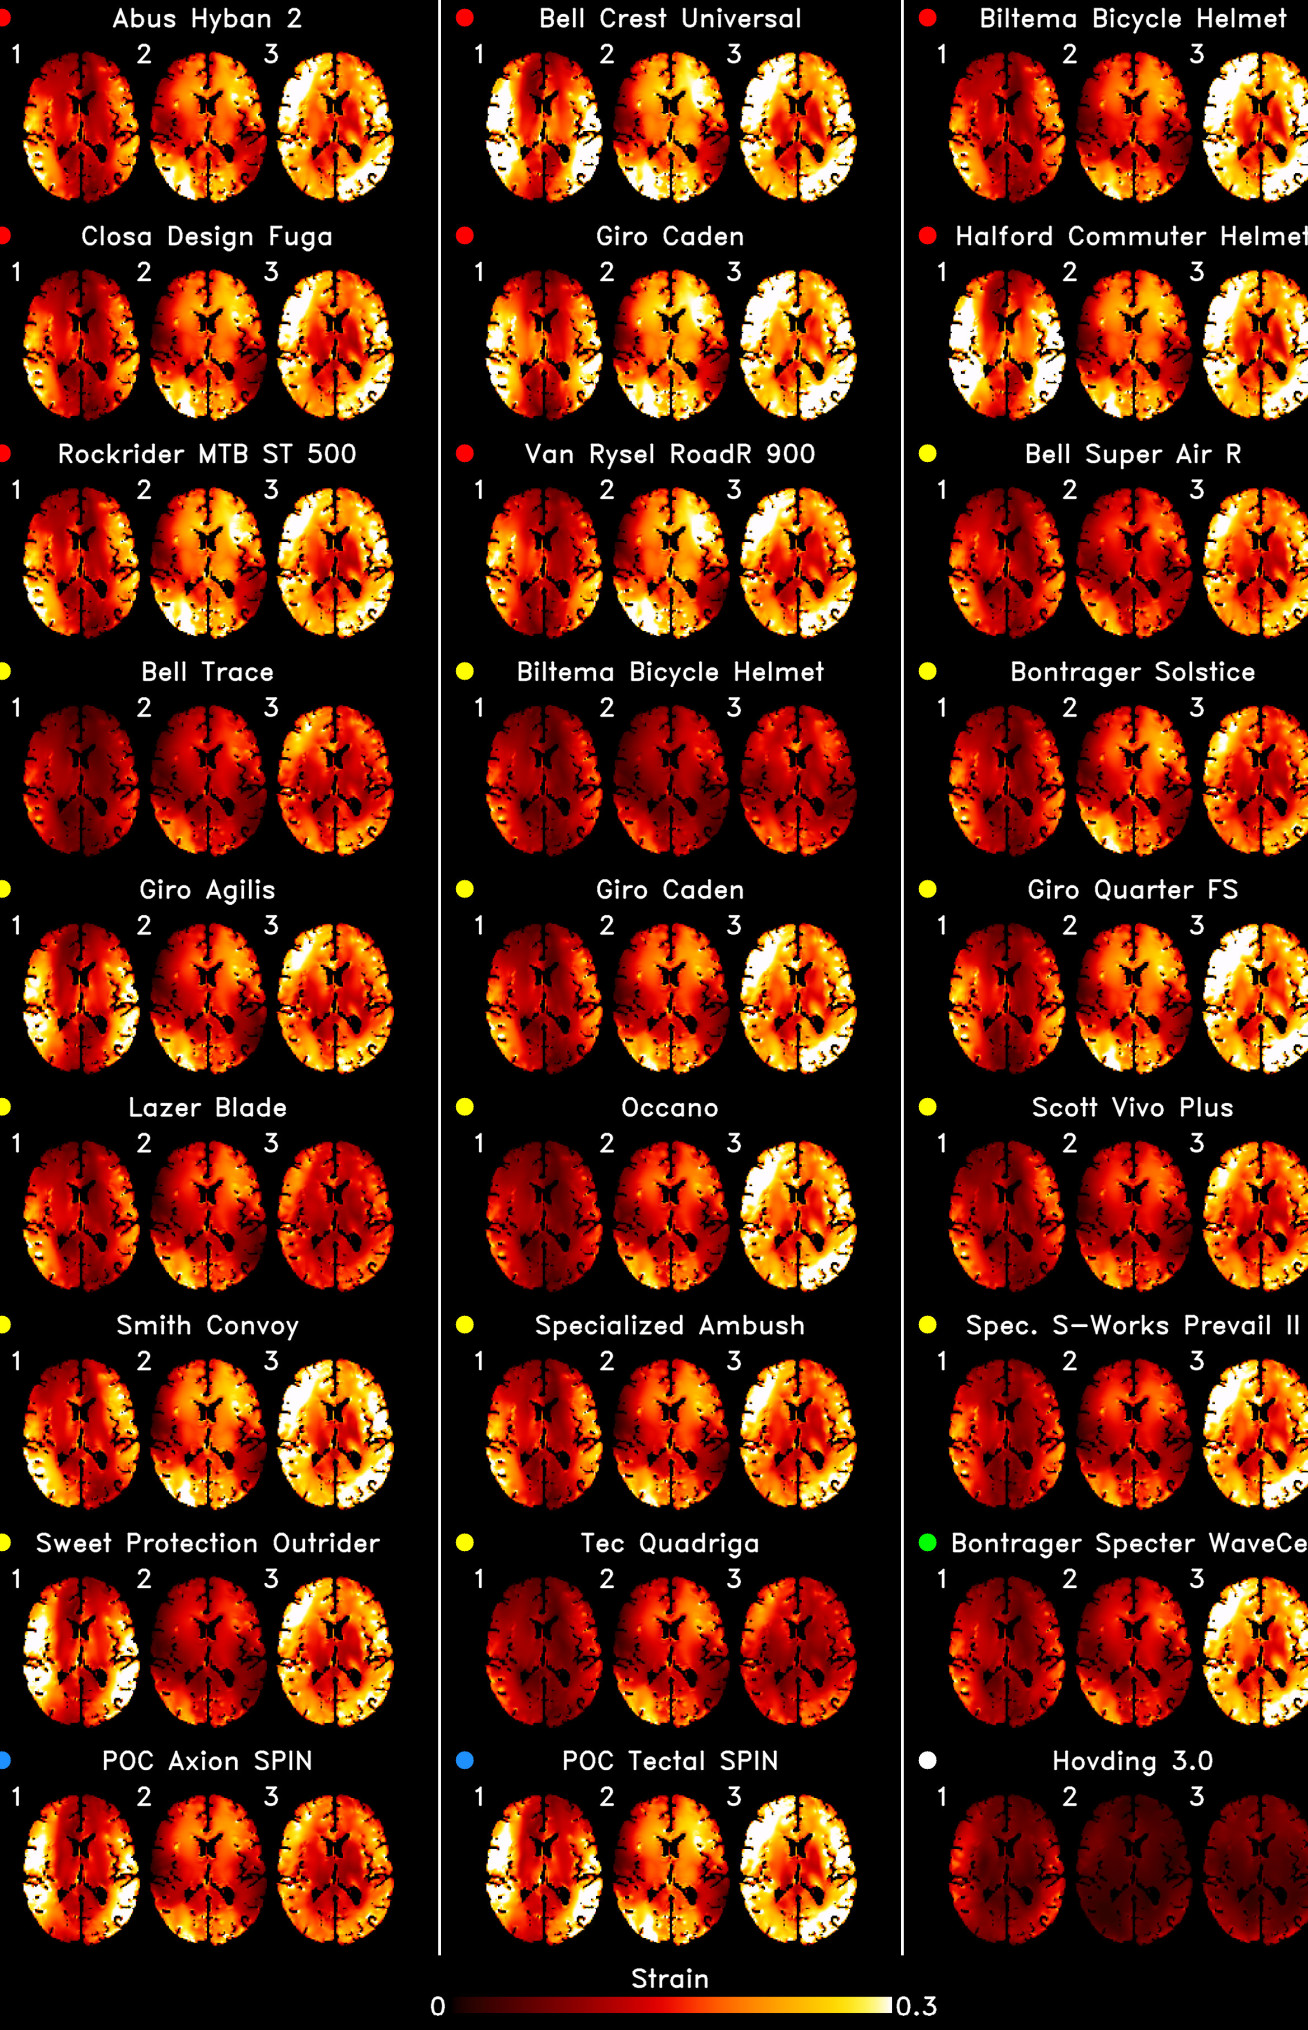

Imaging and computational models depicting the development of brain injury with each helmet and impact type

The researchers used an anatomically detailed model of TBI to predict the distribution of strain across the brain during oblique impacts with each helmet type.

The researchers used this anatomically detailed model of TBI, which was validated against previous cadaver studies, to predict the distribution of strain across the brain during oblique impacts from each helmet type.

They found that newer technologies reduced whole-brain strain compared with older helmets – an effect that was also seen in the corpus callosum and sulci. However, they also found that the effectiveness of newer helmets depended on their technology and location of impact.

Additionally, some helmets which were designed specifically to reduce rotational forces didn’t appear to accomplish their aims. Fady said: “Without a robust, fit-for-purpose testing method and scientific backing, consumers remain underinformed and designers have no specific measures to improve their design decisions.”